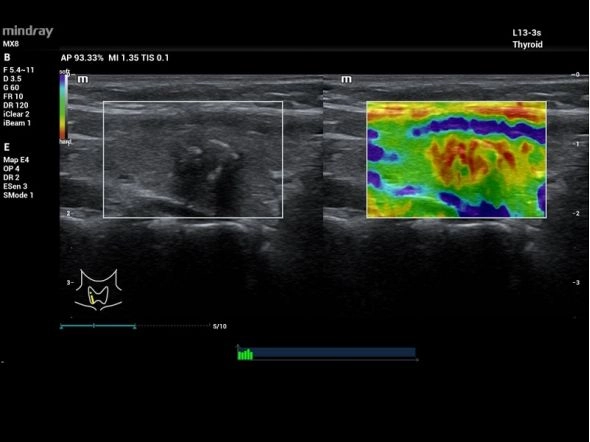

Портативный УЗИ аппарат Mindray MX7 представляет собой прорыв в области медицинской визуализации благодаря платформе ZST+, высококачественным датчикам и усовершенствованному алгоритму обработки данных. Это устройство обеспечивает врачам выдающуюся четкость изображений, что способствует более точной диагностике.

MX7 позволяет проводить точную диагностику на базе передовой платформы ZST+ и обеспечивает эффективный рабочий процесс благодаря настраиваемому сенсорному экрану. Ультралегкий корпус и сверхдолгое время работы от аккумулятора (8 ч.) позволяют использовать его в любых клинических условиях (в мобильных госпиталях, на выездах, при исследованиях у кровати больного). Расширенные функции и инструменты анализа для повседневного рутинного применения.

- Достоверная визуализация: благодаря революционной платформе ZST+, технологии датчиков премиум-класса и усовершенствованному алгоритму обработки данных, УЗИ-сканер MX7 обеспечивает непревзойденную визуализацию для врачей, способствуя точной постановки диагноза.

- Эластография: Компрессионная

Технология ультразвукового сканера MX7, которая обеспечивает быстрое и точное отображение, уменьшает артефакты движения и обладает более высокой частотой обновления кадров.